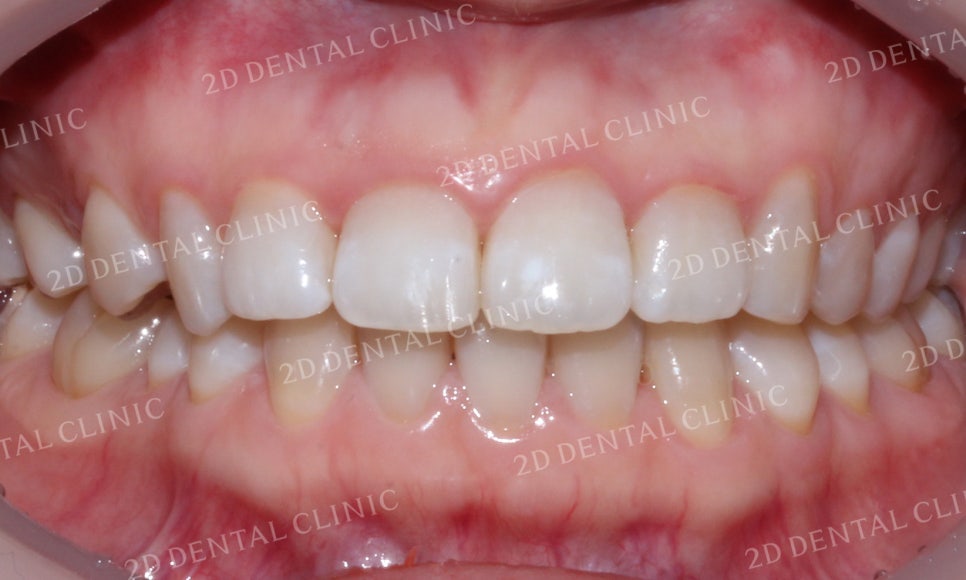

치아 교합 시 입술의 모습입니다.

중절치의 덧니 교정 전 윗입술에서

미세하게 돌출감이 느껴졌었는데요,

교정 후 튀어나온 부분 없이

돌출감이 사라진 모습입니다.

미소 시 전치부 모습입니다.

덧니 증상으로 인해 순측으로

뻐드러지게 나와있던

좌측 중절치가 덧니 교정 후

제자리를 찾은 모습입니다.